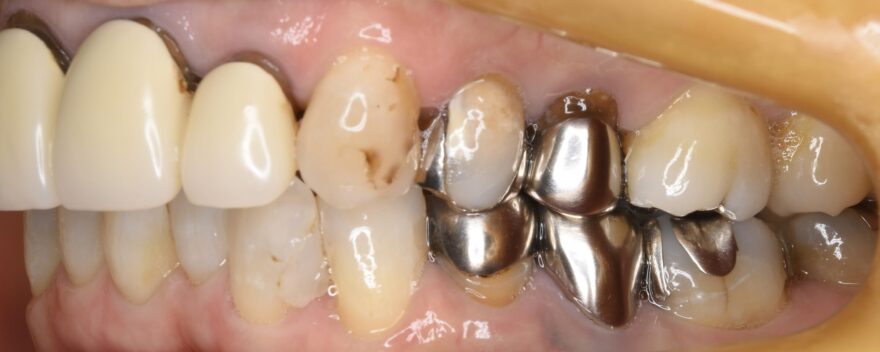

初診時の口腔内写真

銀歯の中が虫歯になっていることがわかります。

こちら側の銀歯も適合の問題を抱えていることがわかります。